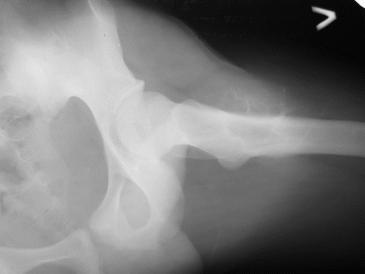

Обратился парень 15ти лет с жалобами на боли в левом коленном суставе. При обследовании обнаружена опухоль в в/з левой бедренной кости.

Проведено КТ заключение( остеохондрома)Подскажите пожалуйста, стоит ли сделать биопсию перед операцией .Кокой операционный доступ и технику операции Вы посоветуете.

Мне кажется, что это не очень похоже на остеохондрому. Может быть неоссифицированная фиброма? Думаю что перед принятием решения об одномоментной резекции либо о трепанбиопсии стоит более детально уточнить рентгенологический диагноз. Вполне может быть что и тактика изменится на выжидательную. У вас есть более качественные снимки РГ и КТ?

По снимку, хоть и не очень хорошего качества,похожн на кисту, гигантоклеточную опухоль, нельзя исключить саркому Юинга. Важно КТ и клиника.